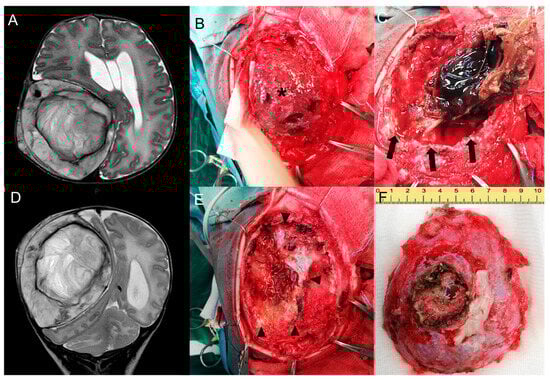

2.2. Endovascular Embolization and Surgical Treatment